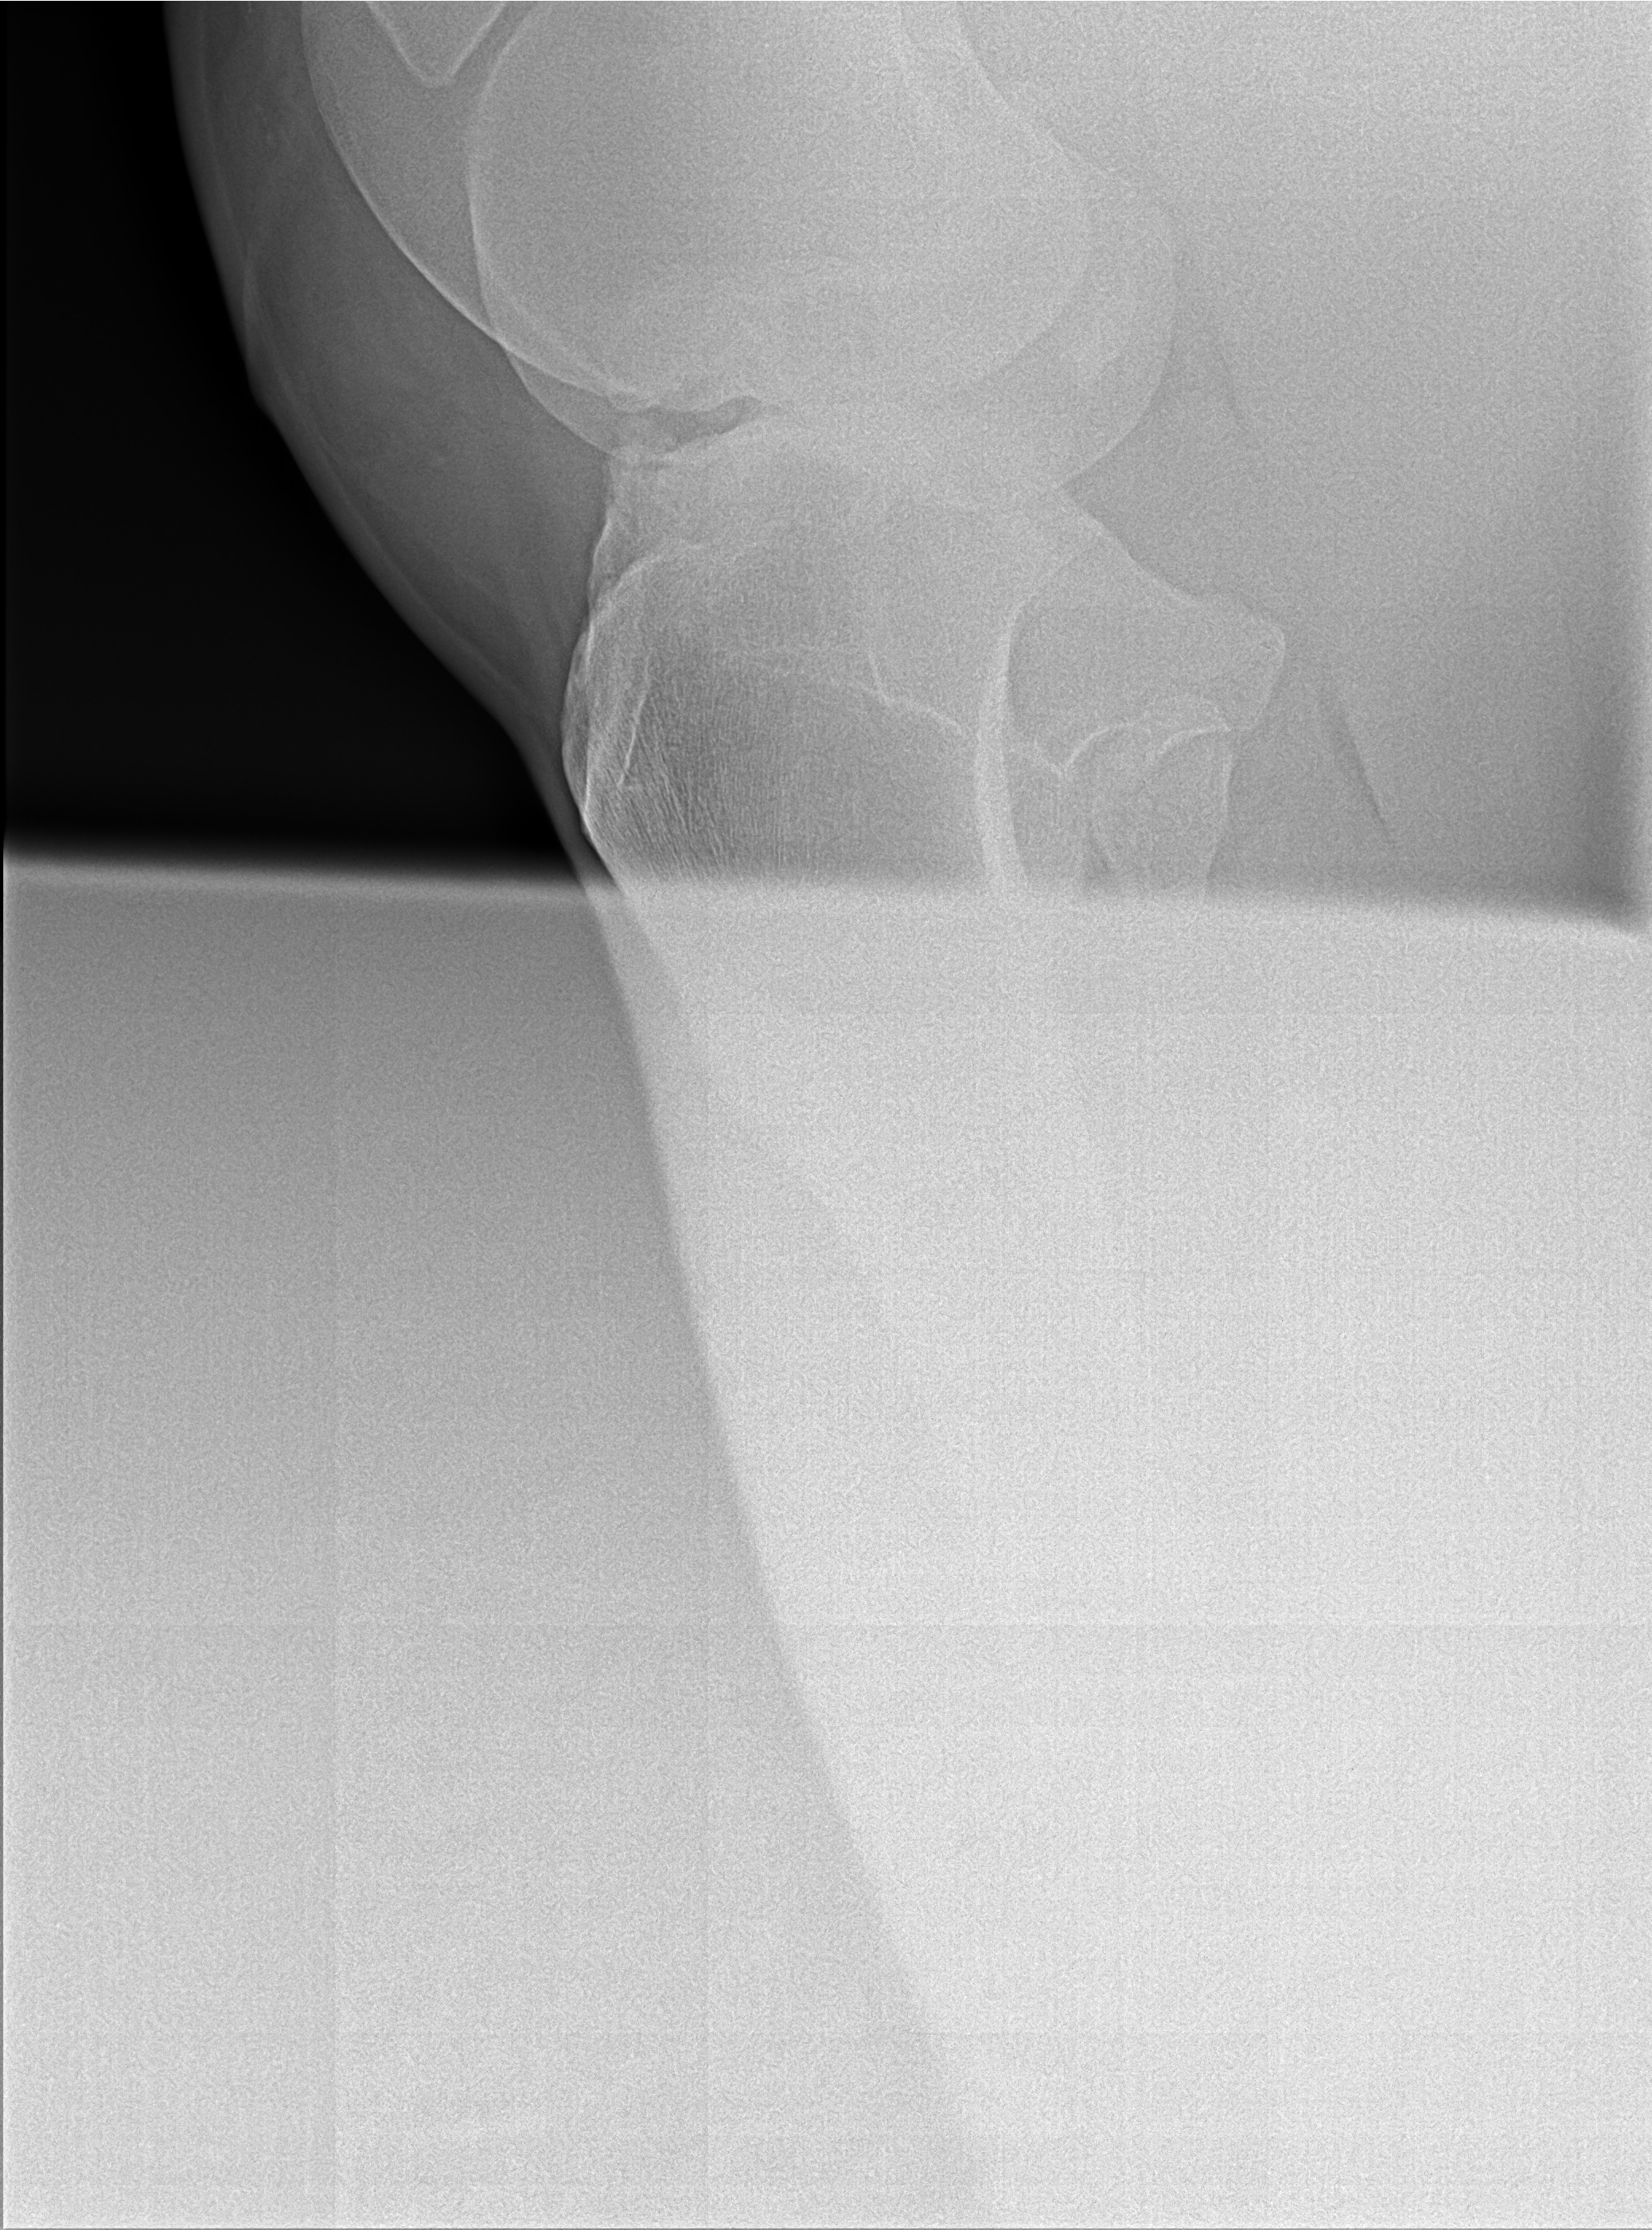

The images from the source dataset had issues and needed to be consolidated into a more usable framework. These issues were mostly due to inconsistencies in practices of radiographers and movement by the animals during radiography that resulted in radiographs with incomplete data, inconsistent image quality, such as varying contrast, brightness and positioning of point of interest or images that failed to meet the prerequisite conditions for this task. Examples of difficult data are shown in Fig. 5.

Most of the source dataset of over a thousand unique knee radiographs were distorted, had poor patient positioning, or were otherwise unfit for annotating. 250 of the original images were of sufficient quality to contribute to this effort. These images were set to have 6 different classes for training purposes, as mentioned and shown in Fig. 4. These were then trained using YOLOv3 [10] and the results of the predicted annotations are shown in Table I. From these predictions the centroids were extracted, which is then used to plot the FTL and MTPL. Then using the method mentioned in Section II, TPA is calculated. Examples of images, the region of interests detection and their respective TPA determination is shown in Fig. 6 and Table I: